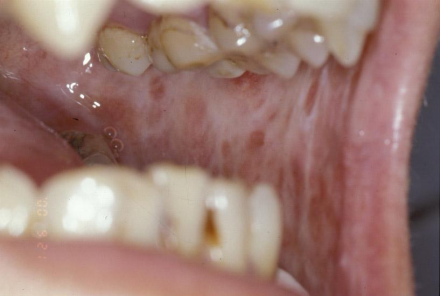

口腔粘膜下纤维性变是一种慢性进行性疾病,与咀嚼槟榔等因素有关。在湖南及咀嚼槟榔地区发病率较高。是一种癌前状态,部分患者合并有口腔癌。主要表现为口腔黏膜灼痛、口干等自觉症状,及进行性张口受限、吞咽困难。

我科对口腔粘膜下纤维性变有丰富的治疗经验,对缓解粘膜灼痛及张口受限的治疗方法,收到了良好的疗效。已开展治疗如:去除致病因素、物理治疗、局部药物治疗、中西医结合治疗、手术治疗等。